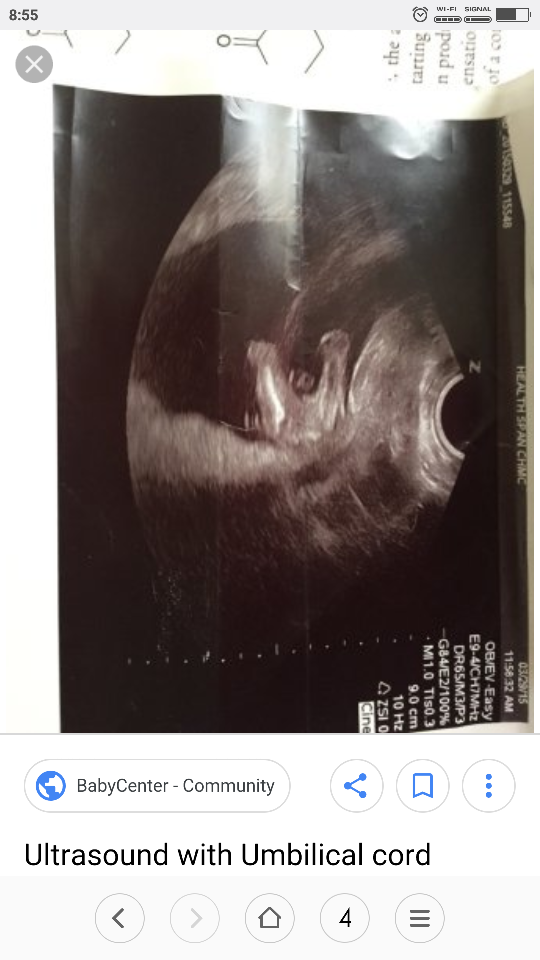

Pepowina na takim zdjeciu tzw "potty shot" nie jeste widoczna.Na dziewczecych potty shot nie widac kompletnie nic- w sensie nic nie odstaje a dziewczynki tez maja pepowine jakby nie patrzec;p

Tak wyglada dziewczynskie potty shot.

z tego samego usg: